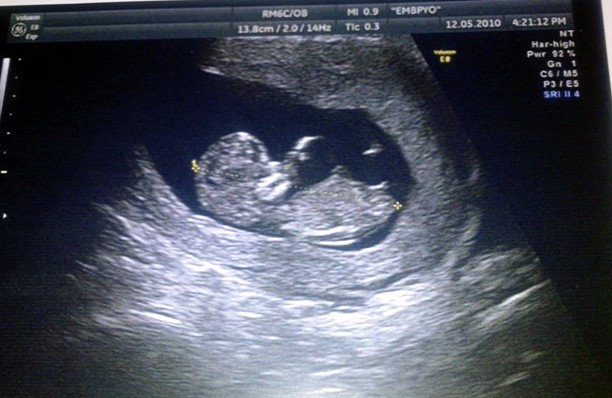

Γύρισα πριν από ένα τρίωρο από τον καλό μου τον γυναικολόγο τον κύριο Μονεμβασίτη, όπου ακούσαμε την καρδούλα του νο2 να χτυπάει γρήγορα και ρυθμικά και το είδαμε το γλυκούλι να κουνιέται ασταμάτητα.

'Οσο για την photo του από τον υπέρηχο σήμερα - με την επισήμανση του γυναικολόγου μου - είναι χαμογελαστή! Δεν πειράζει ladies, κοροϊδέψτε την χαζομαμά, θα έρθει η ώρα που θα πετάξετε και εσείς από την χαρά σας καμία τέτοια χαριτωμενιά.

'Οχι μόνο χαμογελάει, αλλά σας κλείνει και το μάτι. Χα!